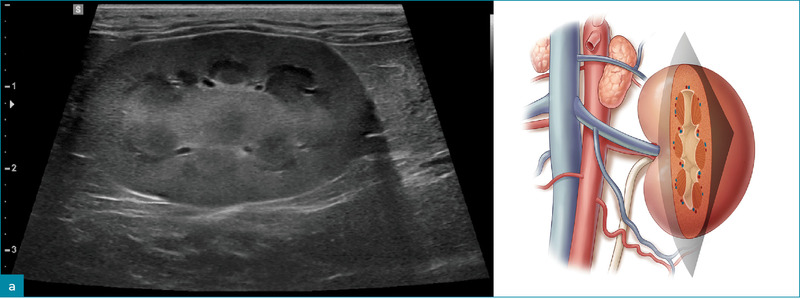

Ryc. 1. Obrazy ultrasonograficzne prawidłowej nerki kota w projekcji: a) strzałkowej, b) dogrzbietowej oraz c) poprzecznej. Towarzyszące ilustracje przedstawiają przebieg płaszczyzn obrazowania.

Ryc. 2. Obraz w projekcji strzałkowej prawidłowej lewej nerki psa, ukazujący hiperechogeniczny zewnętrzny pas rdzeniowy (groty strzałek).